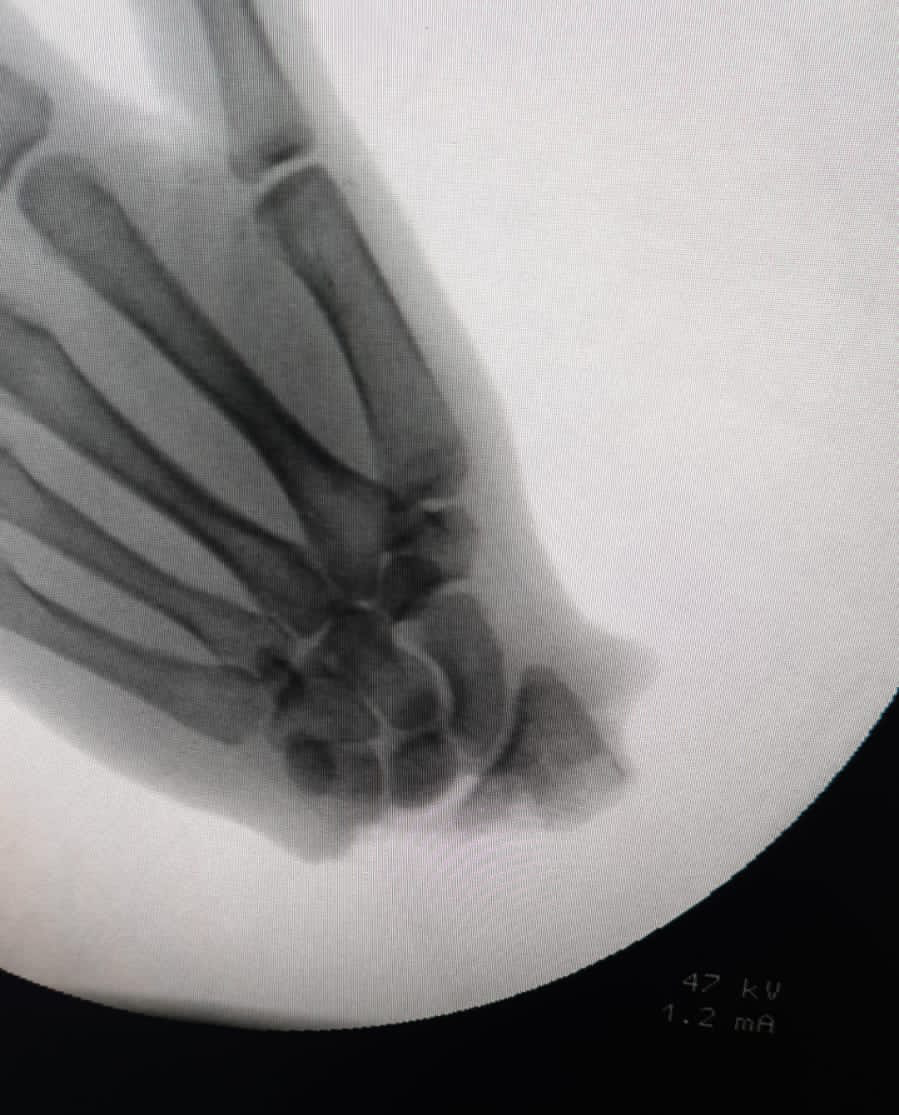

وأوضح  الدكتور عمرو السيد أستاذ جراحة العظام والكسور بجامعة أسيوط ومدير الوحدة أن الحالة لفتاة تبلغ من العمر 16 عاماً من إسنا تم تحويلها من محافظة الأقصر لمستشفى أسيوط الجامعية   مصابة ببتر كامل  لليد في حادث بمنشار تقطيع اللحوم،  وخضعت لإجراء جراحة معقدة لإعادة الزرع عن طريق تشكيل  فريقين للجراحة أختص أحدهما بالعمل الجراحي اللازم في  الجزء المبتور و فريق اختص بالعمل في  ساعد المريضة في عملية جراحية  استغرقت نحو ١٢ ساعة وذلك ضمن نشاط الوحدة المتميز فى إجراء ذلك النوع من العمليات وذلك تحت إشراف الدكتور علاء عطيه عميد كلية الطب ورئيس مجلس إدارة مستشفيات أسيوط الجامعية، ومديرها التنفيذى الدكتور إيهاب فوزى, والدكتور علاء عبد المنعم مدير المستشفى الجامعى الرئيسي.

و حول تفاصيل العملية كشف الدكتور وليد رياض صالح الأستاذ المساعد بقسم جراحة العظام والكسور بجامعة أسيوط ورئيس الفريق الطبى الذى أجرى الجراحة أن العملية تم إجرائها بنجاح رغم وصول الحالة إلى مستشفى أسيوط الجامعى بعد 11 ساعة من الإصابة وهو ما يعد فترة زمنية تتجاوز للمتعارف عليه عالمياً لإجراء مثل ذلك النوع من عمليات التوصيل والمحدد بنحو 6 ساعات فقط,, ولكن بعد عرض تفاصيل الحاله علي اعضاء مجلس الوحد برئاسة الدكتور طارق الجمال مؤسس الوحدة والدكتور عمرو السيد مديرها الحالى تم اخذ قرار جماعي بإجراء عملية التوصيل لإعادة الزرع , مضيفاً أن المريضة حالياً بالعناية المركزة بوحده الجراحات الميكروسكوبية حيث تم الاطمئنان على نجاح استعادة اليد لعلاماتها الحيوية  وجارى متابعة الحالة الصحية للمريضة  .